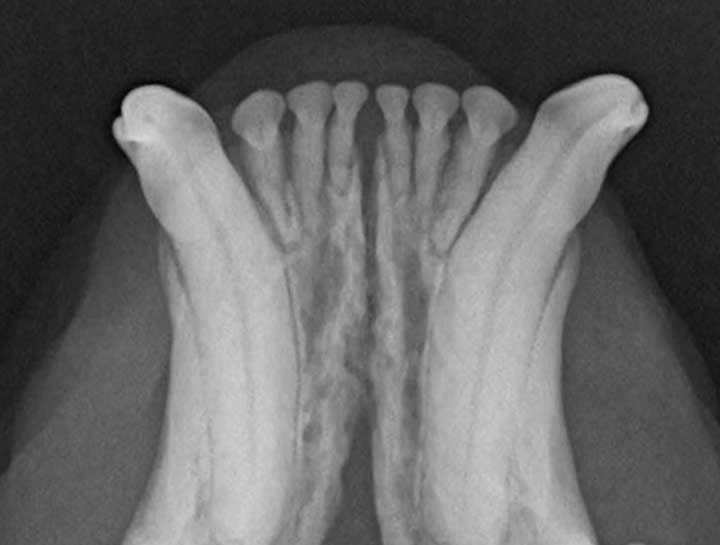

Digital Dental Radiology

Insight into underlying issues.